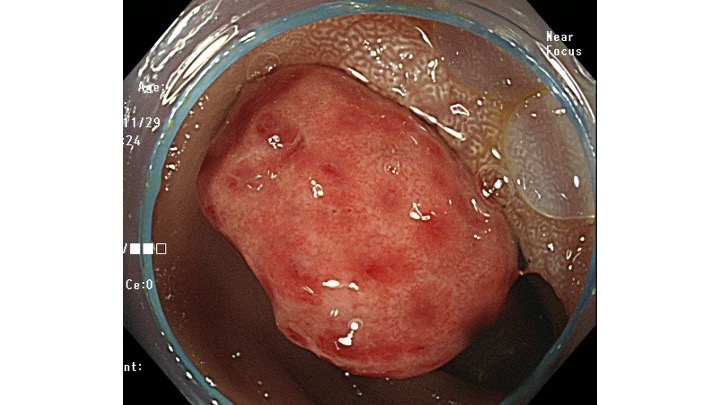

通常観察では、発赤の目立つ凹凸不整な腫瘍性病変をS状結腸に認めます。